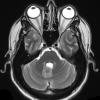

VASCULAR

Cavernous Angioma (10)